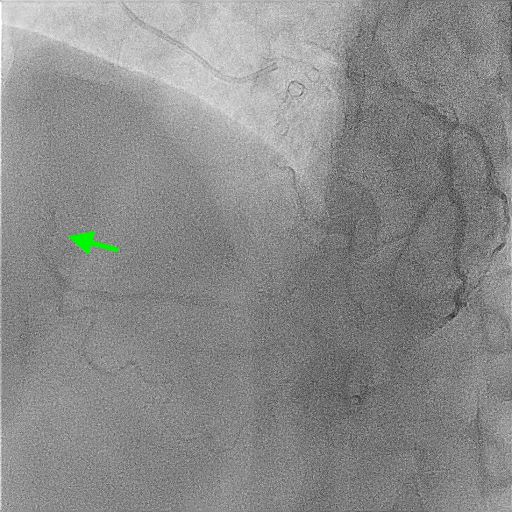

A 51-year-old man presented with stable angina and previously failed right coronary artery (RCA) CTO PCI. During RCA CTO PCI (Figure 1), the wire was inserted into the extraplaque space (Figure 2, Video 1). Intravascular ultrasound (IVUS) showed a hematoma (Figure 3A, Video 2). Live 3-dimensional tip detection IVUS wiring was successful (Figure 4, Video 3). A FineCross microcatheter (Terumo) was placed over the first wire into the extraplaque space and blood was withdrawn by connecting a negative indeflator to the microcatheter. Stents were deployed (Figure 5) and postdilated. Post-IVUS showed almost complete resolution of the hematoma (Figure 3B, C; Video 4) with good results (Figure 6, Video 5).